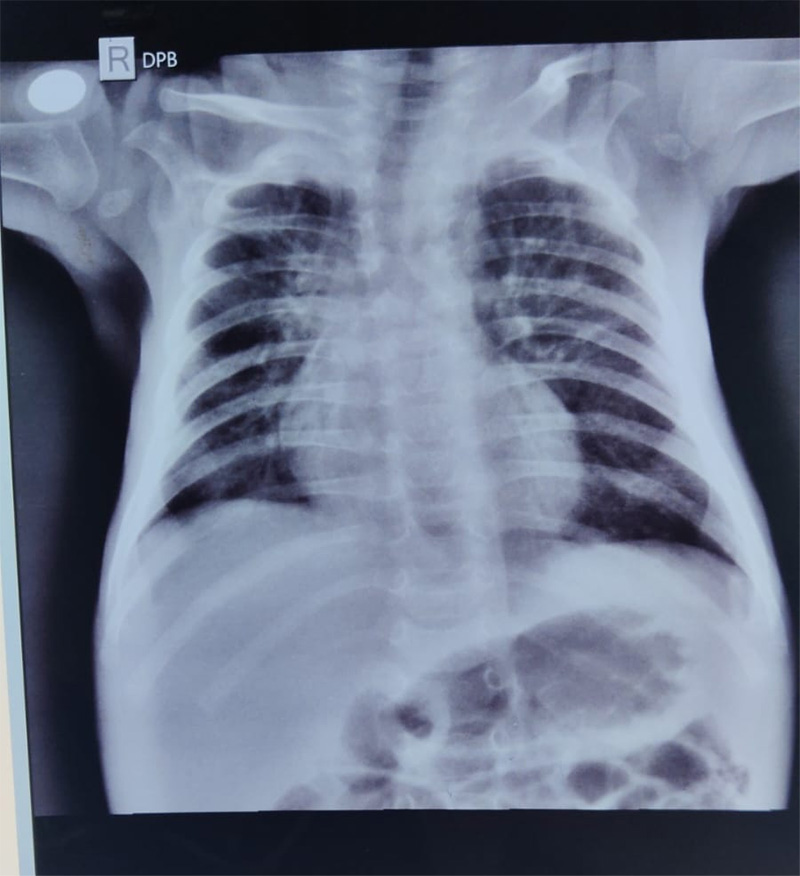

A 2-month-old infant was admitted to the hospital with severe pneumonia. The child had been under inpatient care for over two weeks with persistent symptoms and no significant clinical improvement. Chest X-rays showed progressive worsening of the right lung, and the infant remained dependent on oxygen support.

• Radiological evidence of right lung consolidation

• Chest X-rays post-bronchoscopy showed clear re-expansion of the affected lung area